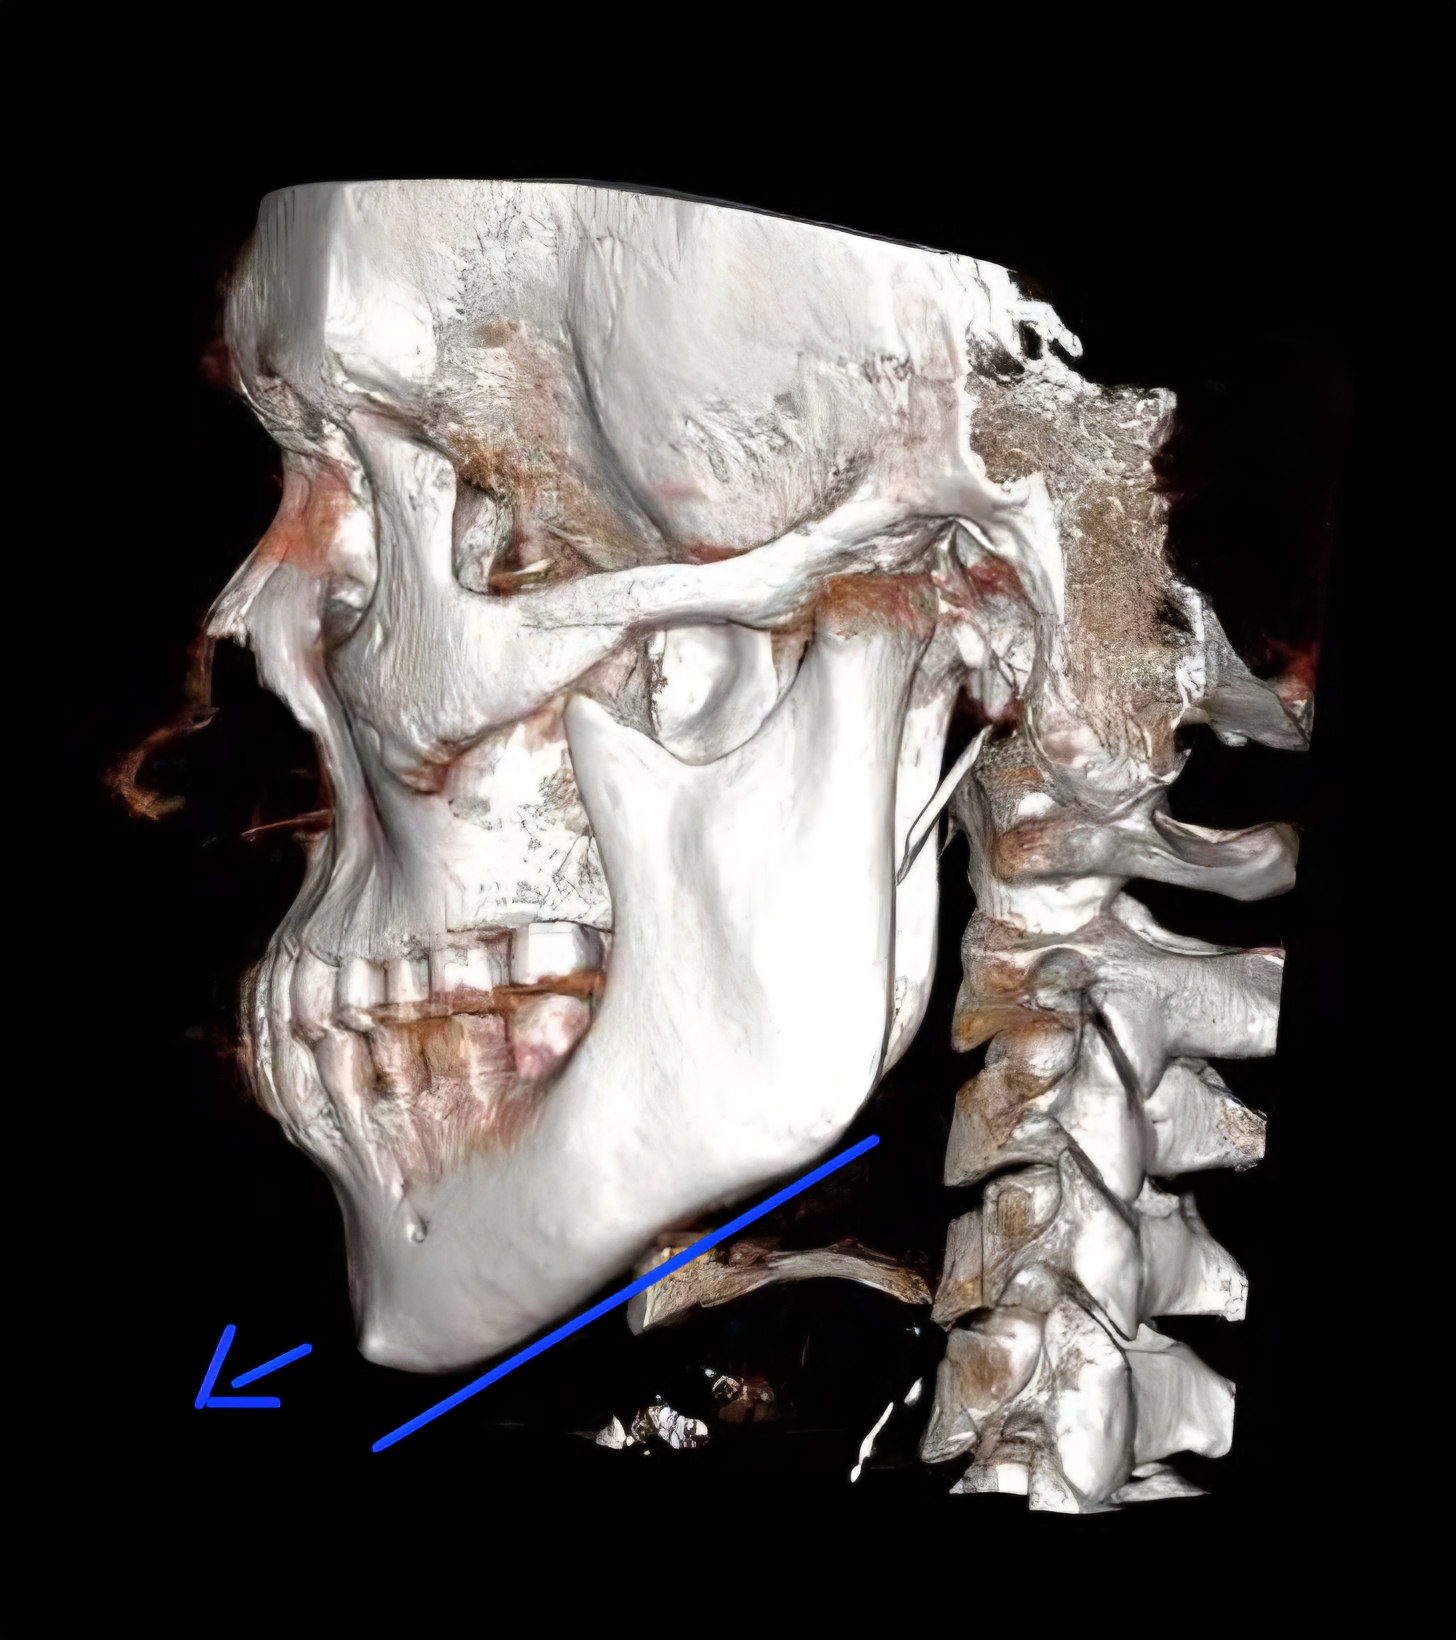

huge movements from ram no bone graft

huge movements from ram no bone graft